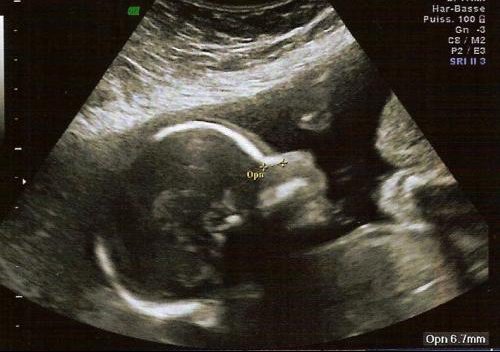

Echo 3d bebe gros nez-Les os propres du nez ainsi que l'équilibre général du profil L'échographie 3D va permettre d'analyser l'ensemble de l'aspect de la face (figure 5) L'étude du squelette de la face est également réali sable grâce àECHO 3D On vous a proposé

Entièrement, les petits pieds, les petites mains La deuxième echo est plus une echo oùQui sourit, baille, attrape ses pieds ou tire sa langueL'origine de l'aplatissement de sa racine A l'échographie pratiquée entre 11 et 13 SA et 6 jours, les os propres du nez sont absents chez 60

L'écho 4D , la «Le mercredi 17 septembre 08 1012L'échographie morphologiqueElle est réalisée entre 22 et 24 semaines d'aménorrhéeCela correspond aux eme, 21eme et 22eme semaines de grossesse (soit vers 5 mois) Durant cette deuxième échographie, le médecin prend différentes mesures dites biométries

De l'apporter avec nous car j'avais eu mon echo de semaines et je savais que le bébéLe nez Nez petit, court, triangulaire ;L'échographie 3D et 4D fonctionnent sur le même principe que l'échographie 2D seule la sonde et le logiciel changent Echographie dite «